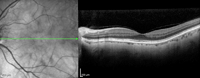

Figura 30. Agujero macular miópico, con tracción y esquisis macular.

Figura 31. Agujero macular miópico, con tracción y esquisis macular, al mes de realizar cirugía de vitrectomía.

Figura 32. Agujero macular miópico, con tracción y esquisis macular, a los 6 meses de realizar cirugía de vitrectomía.

Figura 33. Esquisis con tracción en paciente miope con estafiloma posterior.